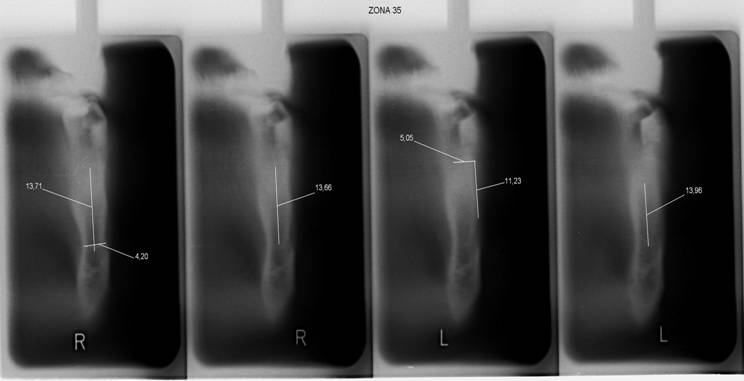

Tomografia Assiale

Figura 17

Consiste in un’elaborazione di dati acquisiti mediante tomografia computerizzata.

La metodica presenta il grande vantaggio di poter analizzare spontaneamente la qualità ossea della corticale e della midollare, e di poter rilevare l’altezza e il diametro della sezione ossea.

Figura 18